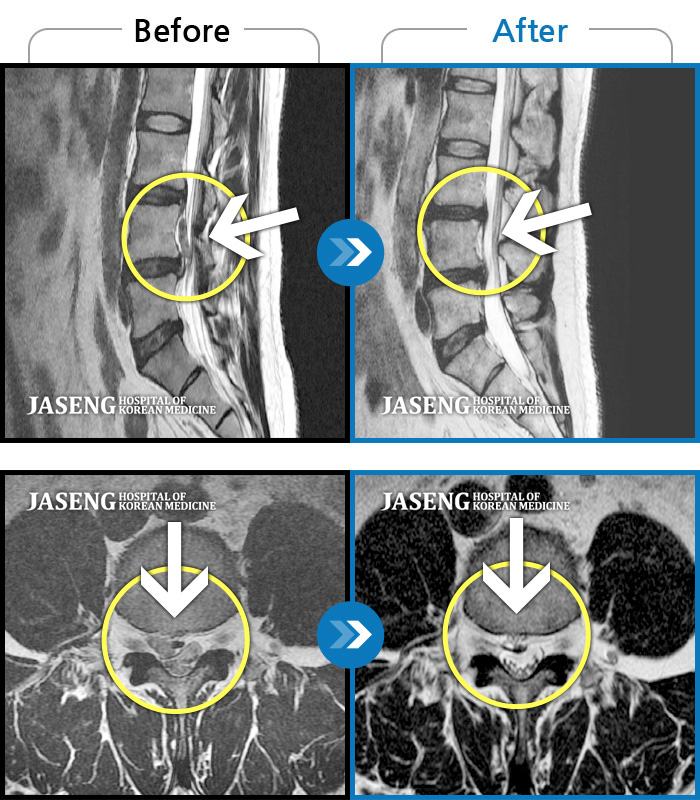

허리디스크

강남 · 강만호 원장

허리통증 및 왼쪽 다리 통증으로 운전이 불가능했습니다.

촬영시기

2023.10.16 ~ 2024.10.14

2024.10.23

조회수 457